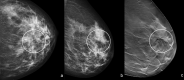

Radial scar (RS) or complex sclerosing lesions (CSL) if > 10 mm is a benign lesion with an increasing incidence of diagnosis (ranging from 0.6 to 3.7%) and represents a challenge both for radiologists and for pathologists. The digital mammography and digital breast tomosynthesis appearances of RS are well documented, according to the literature. On ultrasound, variable aspects can be detected. Magnetic resonance imaging contribution to differential diagnosis with carcinoma is growing. As for the management, a vacuum-assisted biopsy (VAB) with large core is recommended after a percutaneous diagnosis of RS due to potential sampling error. According to the recent International Consensus Conference, a RS/CSL lesion, which is visible on imaging, should undergo therapeutic excision with VAB. Thereafter, surveillance is justified. The aim of this review is to provide a practical guide for the recognition of RS on imaging, illustrating radiological findings according to the most recent literature, and to delineate the management strategies that follow.